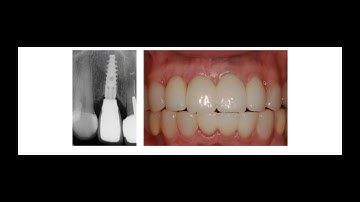

Socket shield for Dental implants- What Should You Know